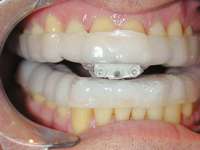

Treatment of these side effects involves joint and muscular therapy, the use of a leaf gauge on wakening as part of an occlusal maintenance program, and palliative therapeutic measures. Patient monitoring must be initiated with adaptation to the appliance, followed by guiding titration31 (Figure 15). The patient and dentist must work together and make well-advised risk vs benefit decisions during the treatment process. Too often there is a tendency for the dentist to be overly concerned about dental changes that may not affect function or esthetics, causing therapy to be abandoned when it is essential to the patient’s health. The treating dentist must be aware of the anatomy and physiology of the temporomandibular joint so that strains created in the joint can be recognized and treated as opposed to aborting oral appliance therapy, possibly prematurely.

Figure 13 The SomnoDENT is made by SomnoMED. The quality control of this appliance is excellent, and it is durable and comfortable.

Figure 15 A key is used by the patient who is given a specific schedule to titrate the appliance in the anterior direction.